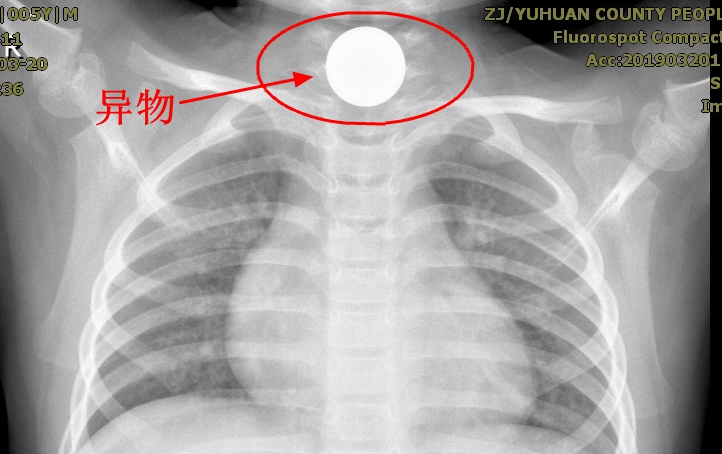

“医生,我家孩子好像吞下了什么东西,快点帮忙给想想办法!”3月20日晚上10点多,一对年迈的老人抱着5岁的孙子跑进玉环市人民医院急诊科焦急地说道。患者小成指着自己的喉咙,不时的感觉恶心想吐,异物感明显,这可急坏了家中的老人。

值得庆幸的是,经拍片检查,异物并没有卡入气道,否则将是致命的危险。急诊科医生在了解患者情况后立刻联系消化内科主任裴希军,裴主任和其他医生一起对患儿异物位置及身体情况等进行了初步评估,行气插全麻下取异物术。

经过医生们的通力配合,在短短2分钟,就顺利取出卡在食管的异物,竟是一枚硬币,最终小成家人悬着的心总算放了下来。

原来,当晚家住海山的小成在家中玩耍,好奇的找到了一枚硬币,一不小心硬币顺着嘴巴滑了下去。因为卡在喉咙难以忍受,起初自己想着去扣嘴巴,但没用成功,这才想到向奶奶救助。